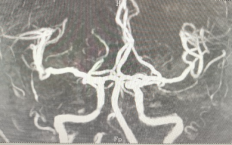

影像学检查:如B型超声成像、经颅多普勒检查、CT血管造影、磁共振血管造影、脑血管造影等,用于明确血管狭窄的部位、程度和原因。